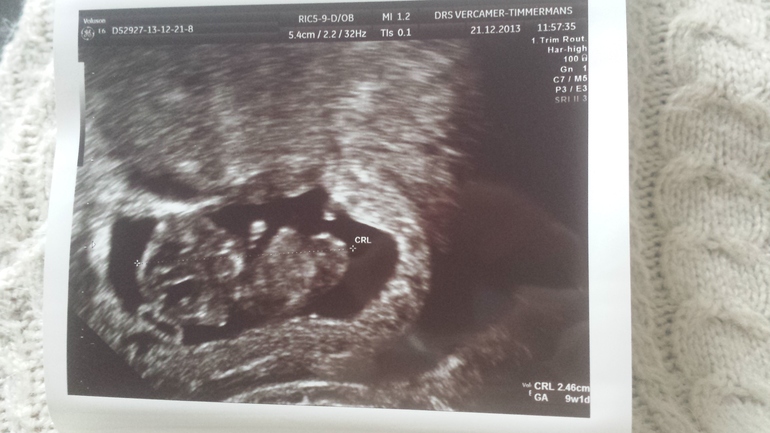

У меня цикл длинный очень и если считать от М то уже примерно 12 недель будет. Но хорошо что я заграницей живу тут врачи на это не обращают внимания и не запугивают тем что плохое развитие и не успеваете... они просто высчитали по О и по ХГЧ. Врач говорит что все супер и развивается по срокам без отставаний

У меня 43 дня так что тут очень длинный цикл. Я раньше думала что не регулярный он у меня так как не следила за своим циклом а после В начала следить и получалось всегда от 41 до 43 дней не меньше и не больше. Наши врачи уже бы говорили что нужно делать аборт так как плод не развивается по срокам... у моей знакомой такая ситуация была

Такой щекастенький)))) весь в папу)))) смотрела фотки родственницы одной на этом же сроке у них не такие щечки)))))